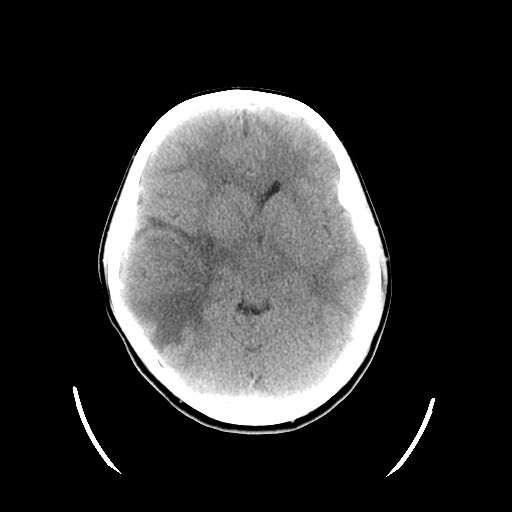

Se realiza una TC craneal urgente con el siguiente resultado: tumoración intraaxial temporal derecha de aproximadamente 39 × 44 mm, con edema perilesional que colapsa asta frontal del ventrículo ipsilateral con dilatación de asa temporal y desviación discreta de línea media con captación de contraste periférica.